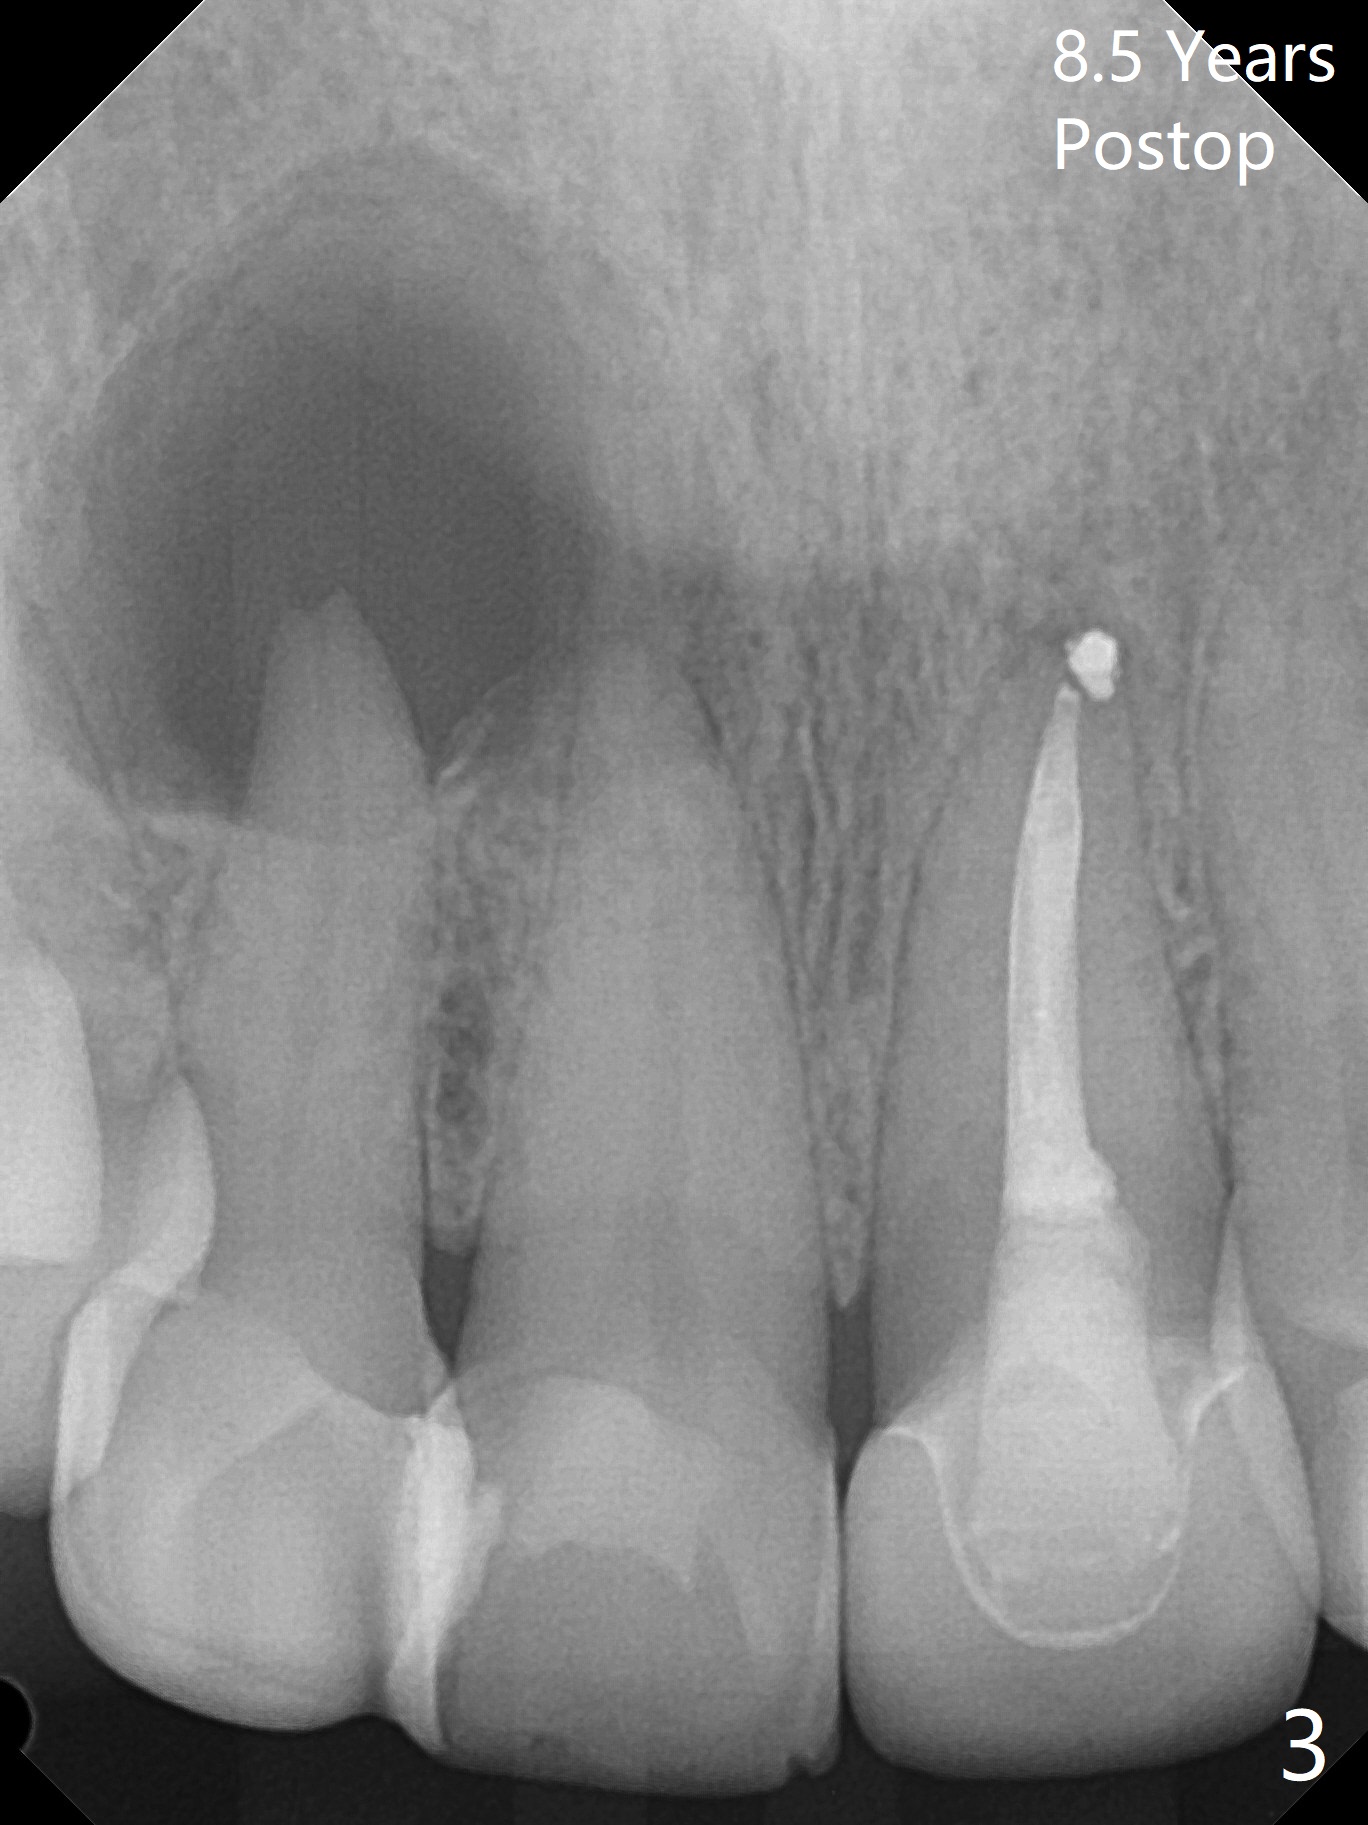

A 47-year-old woman (dental phobic) presented to clinic 9.5 years ago with periapical radiolucency (PARL) at #7 and 9 (Fig.1). RCT was done at #9 because of fistula and symptom 6 months later (Fig.2). While PARL increases at #7 without symptom, that at #9 disappears 8.5 years postop. Three months later, the patient returns for #7 RCT because of the abscesses (Fig.4 *) and pain. Intraop PA is taken with a 30/.06 rotary file in the canal with 19 mm working length (Fig.5). After use of #15 hand file for 20 mm, Ca(OH)2 paste is applied in the canal. When the rubber dam is removed, the abscesses enlarge (Fig.6), which may be related to sodium hypochlorite leakage. A dental explorer is used to try to find a bony opening to the large PARL without success (Fig.7). A postop PA reveals the leakage of Ca(OH)2 paste (Fig.8). Review of the preop PA (Fig.3,9) and intraop PAs (Fig.5,10) shows possible apical resorption and open apical foramen, which is the basis for the paste leakage (Fig.8,11). Careful analysis (with magnification and room light off) of pre- and intra-op PAs should be able to avoid use of #15 hand file out of apical constriction and the complication. The abscess has receded 1 month later (Fig.12). The paste has been resorbed 1 month later (Fig.13). A 30/.06 Gutta Percha is inserted at 18.5 mm (Fig.14 vs. 30/.06 file at 19 mm, 15 file at 20 mm last visit). Fig.15 is the final PA after closure of the access with composite (Fig.15).